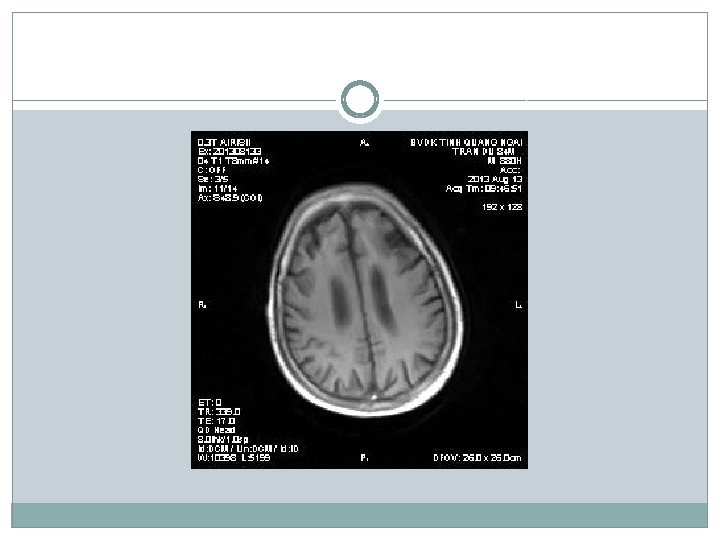

�Siêu âm có nang thận phải # 34 mm �X-quang tim phổi bình thường; thoái hóa cột sống thắt lưng �Điện não: chủ yếu sóng chậm Theta, ưu thế vùng trán (T) �Điện tim bình thường �CT scan não: Nhồi máu não thùy trán (T) �MRI não: Nhồi máu thùy trán (T), teo vỏ não thùy trán + não thất giãn nhẹ

Chẩn đoán �Tuy nhiên có điểm chưa phù hợp trong chẩn đoán bệnh Parkinson: khởi bệnh run cả hai bên đối xứng; hình ảnh học MRI cho thấy có teo vỏ não, có biểu hiện rối loạn tâm thần sớm